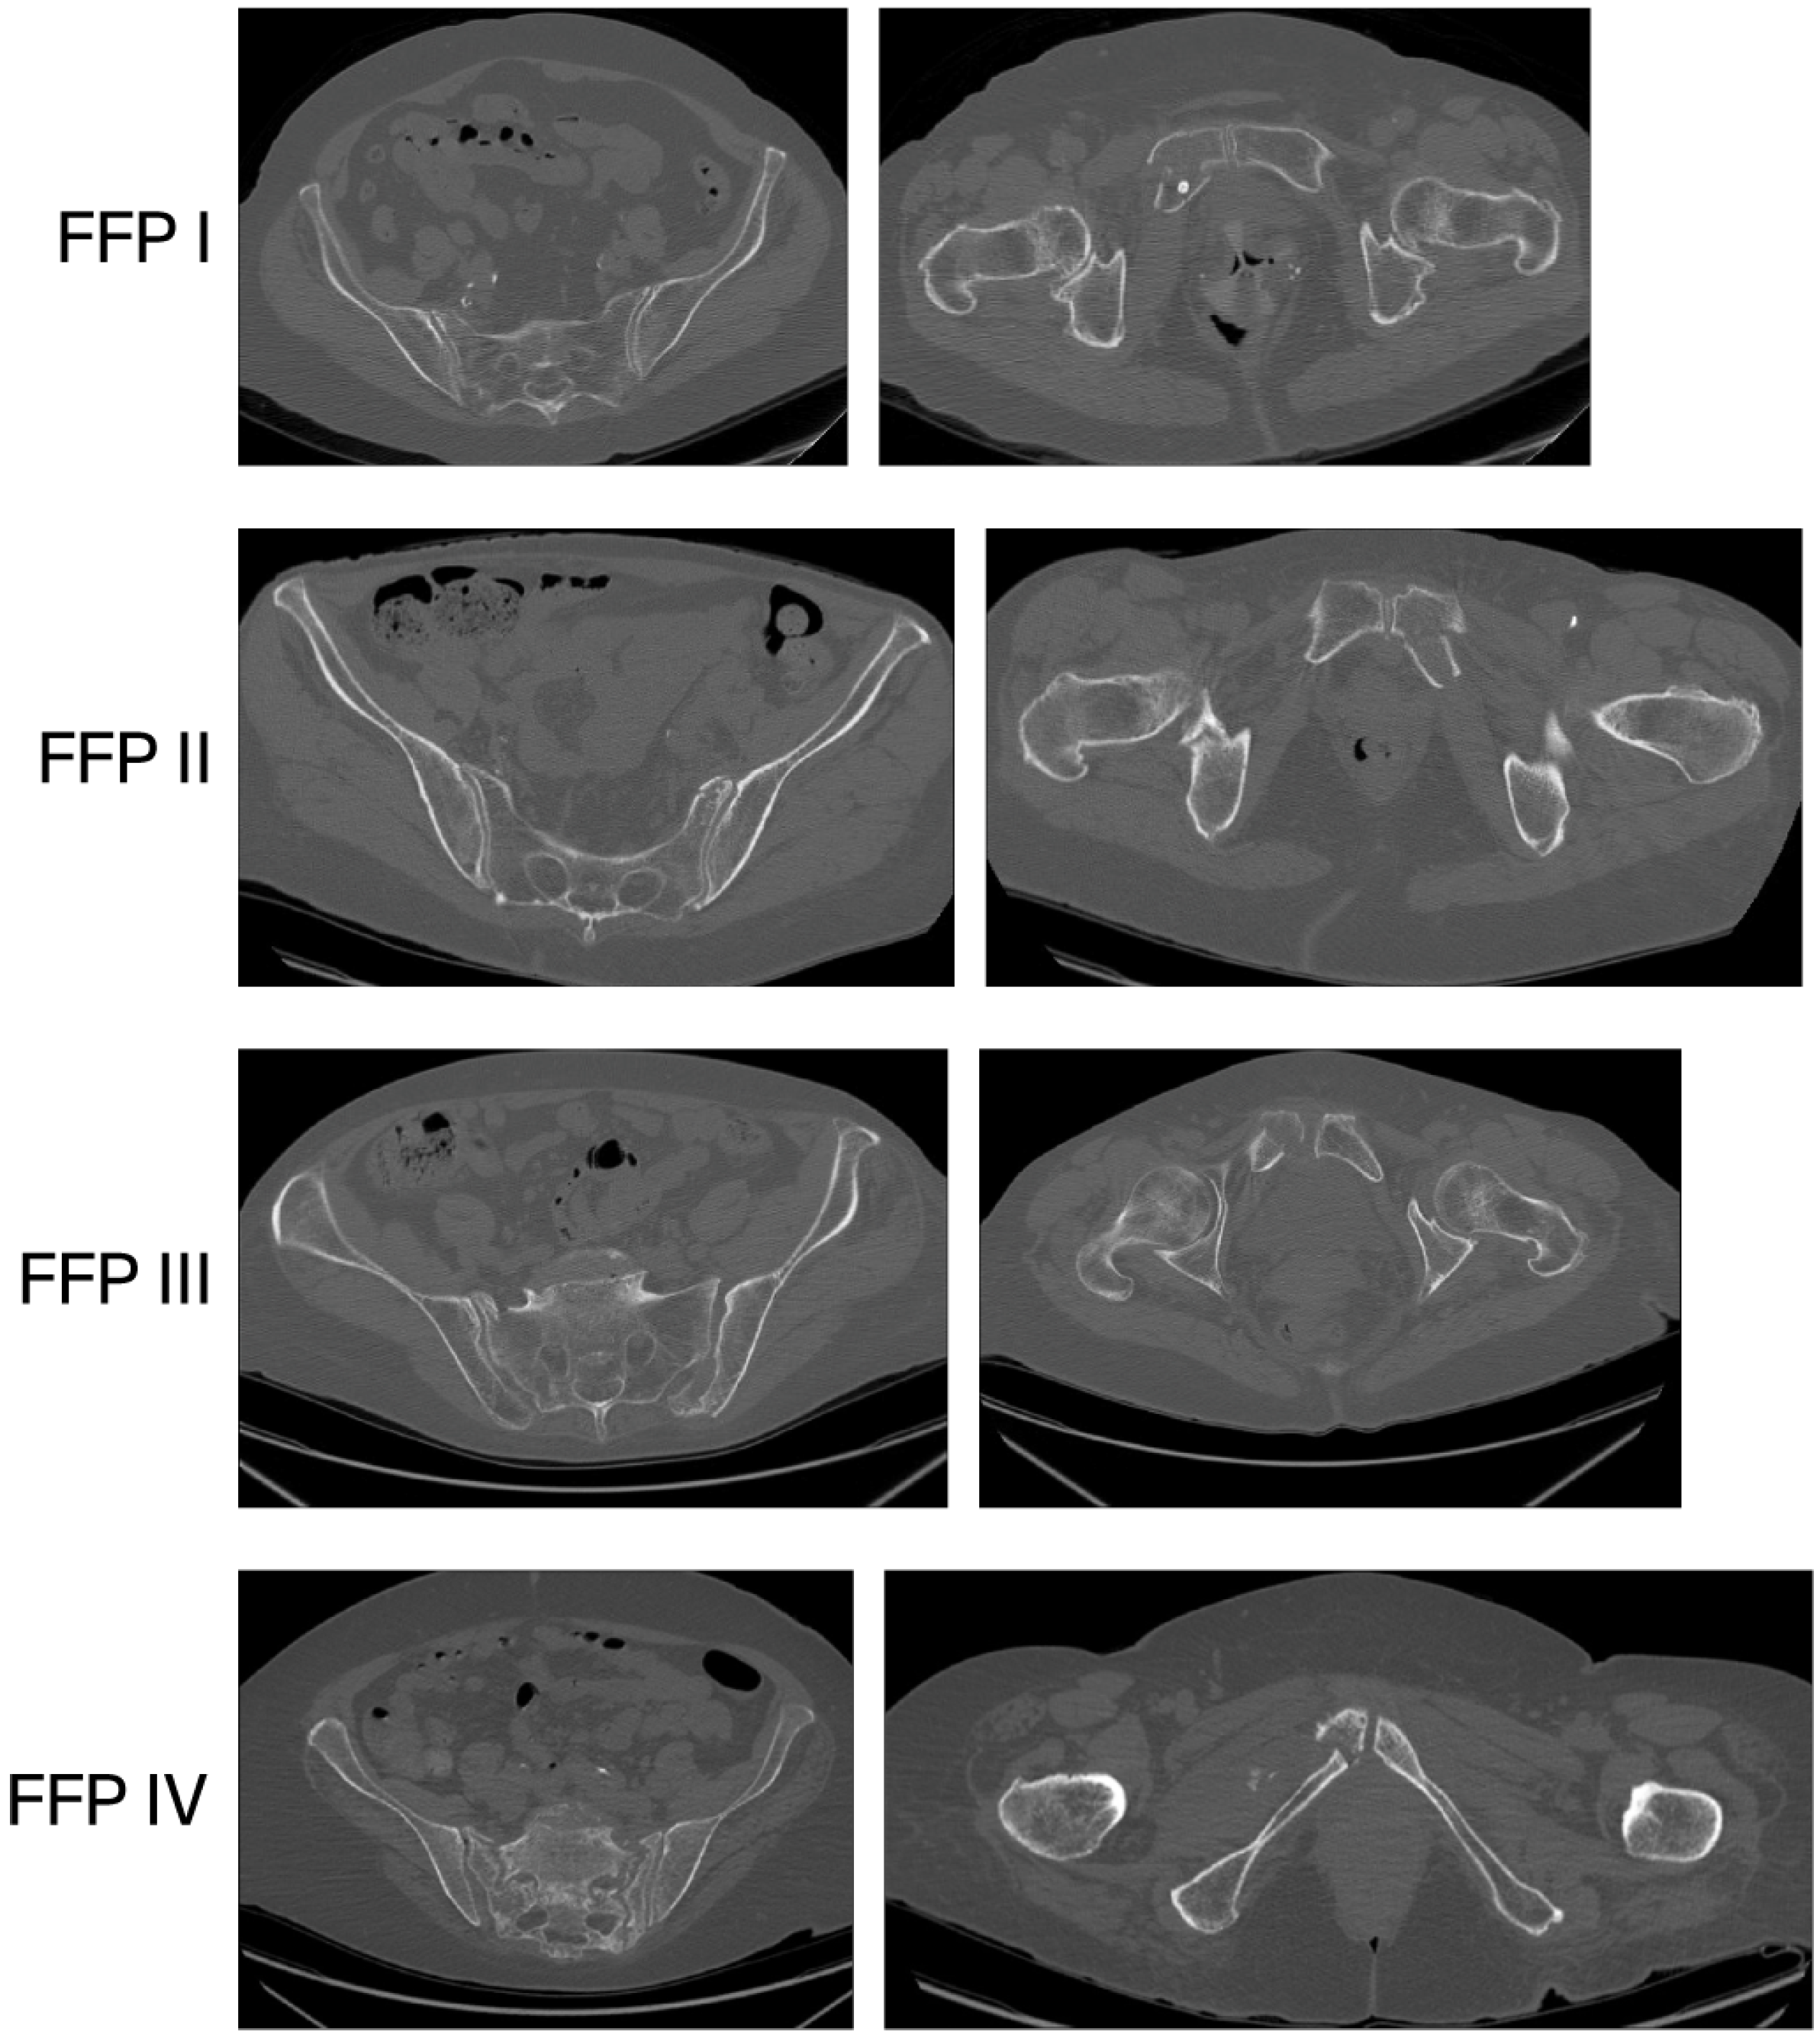

Every patient was examined with CT to assess the posterior pelvic ring, and in 62 (60.6%) cases, the posterior ring was fractured. According to the aforementioned Fragility Fracture of the Pelvis Classification, 37 (37.4%) fractures were assessed as type I, 42 (42.4%) as type II, 10 (10.1%) as type III, and 10 (10.1%) as type IV (Figure 2 and Figure 3).

According to the aforementioned Fragility Fracture of the Pelvis Classification, in our study, 37 (37.4%) fractures were assessed as type I, 42 (42.4%) as type II, 10 (10.1%) as type III, and 10 (10.1%) as type IV. The fracture type distribution is different from that presented by Banierink et al. [24], where type I was present in 60%, II in 27%, III in 8%, and IV in 5%. In Rommens and Hofmann’s original paper [22], they observed a 51.8% prevalence of type II fractures.

Figure 3. FFP types.